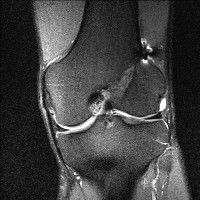

무릎 mri 간단히 봐주실 수 있으시나요 ㅠㅠ

안녕하세요 8년전 십자인대 수술하고 최근 무리한 운동에 무릎 불편감이 생겨서

mri 찍었습니다.

진단결과는 첫 찍은 병원에서 활액막염 이라는 진단을 받았습니다. 혹시 봐주실 수 있으실까요?

올라온 MRI가 단편적이라서 정확한 진단에 어려움이 있지만 십자인대에는 큰 이상이 있지는 않은것 같으며, 무릎관절내 물이 있는 것으로 보아 활액막염의 진단이 맞을 것 같습니다.

하지만 단편적인 영상이기 때문에 촬영병원에서 정확한 판독지 등을 받으시는 것이 좋겠습니다.